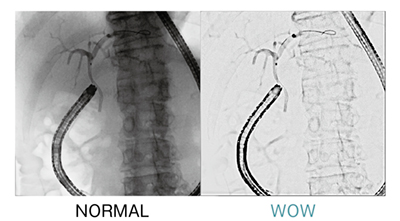

■見えないから,視える驚き。「WOW*4」

透視下でガイドワイヤなどのデバイスを浮き出して見やすくする透視画像技術である(図3)。背景部に減衰処理を施すことで,椎体に重なるデバイスの視認性を向上させることができる。

図3 WOW(背景部減衰処理)